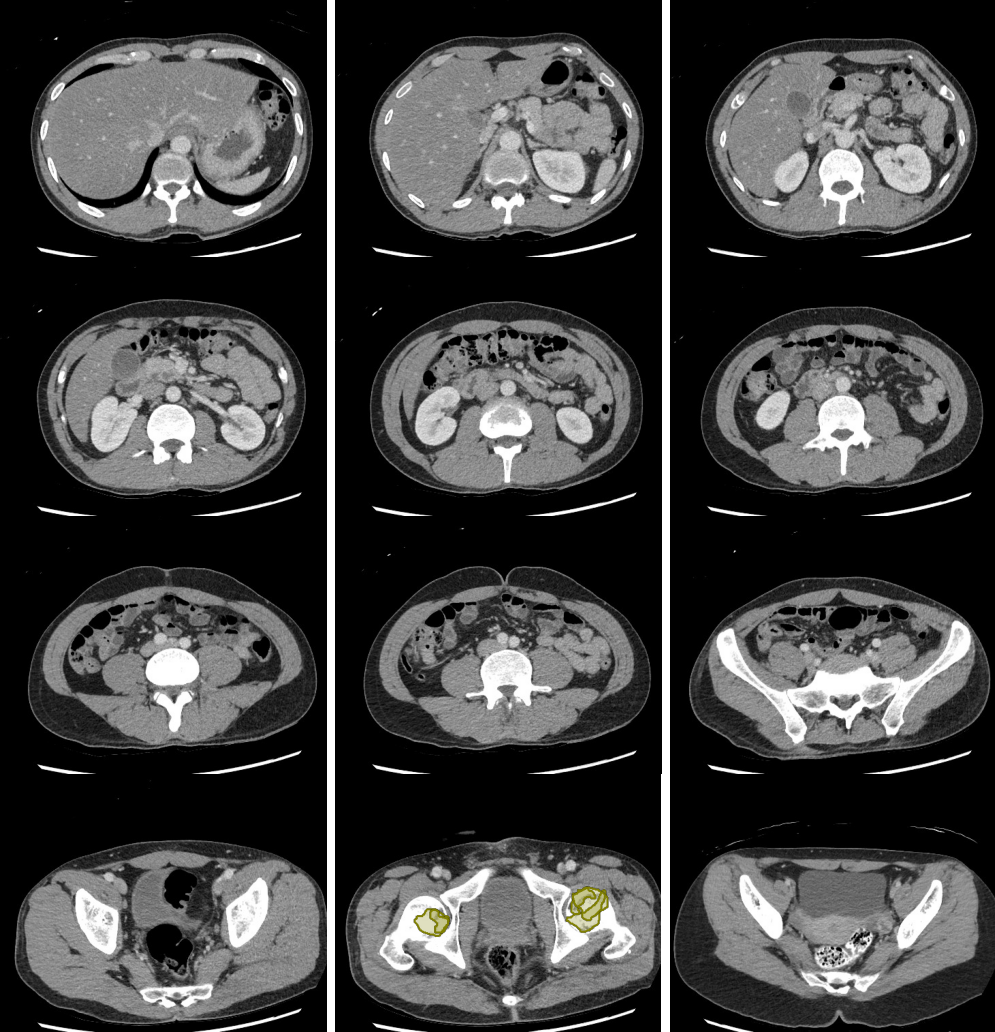

- Look carefully for small stones in the ureter/UVJ. Familiarize yourself with the normal location of the ureterovesical junctions and the configuration of the distal ureter to discriminate phleboliths from potential distal ureteral calculi

Stones

Slice 1

Slice 2

Slice 3

Slice 4

Slice 5

Slice 6

Slice 7

Slice 8

Slice 9

Slice 10

Slice 11

Slice 12